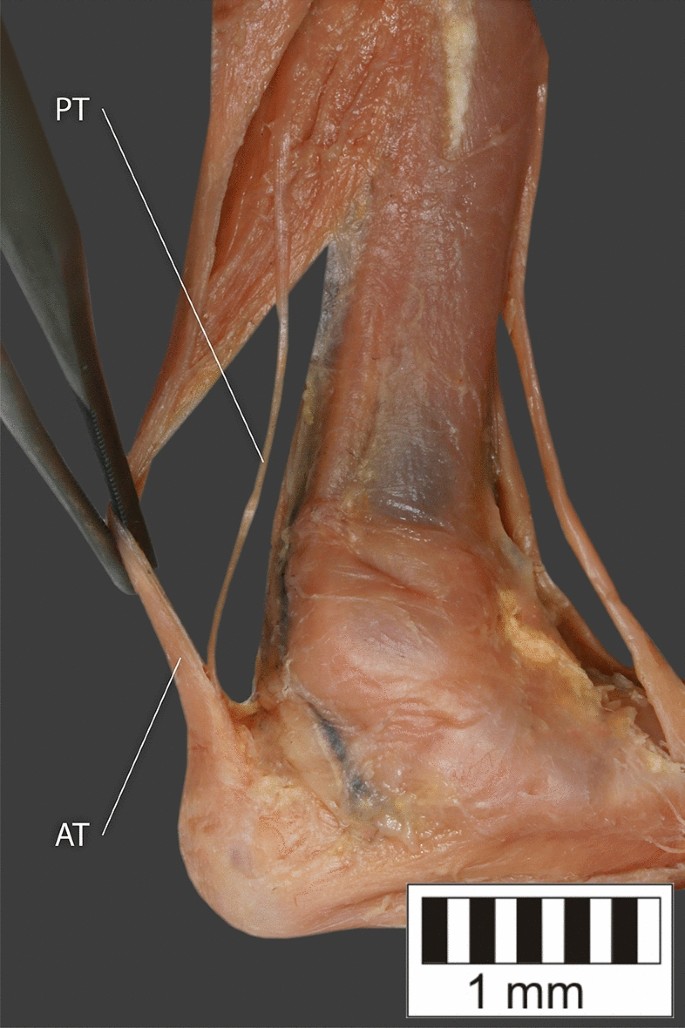

Type VII—the tendon inserts at the Achilles tendon. Missing in the studies by Olewnik et al.4,11. Fig. 2A.

Type VII—Present on 10 lower limbs (10.87%). The tendon inserts at the Achilles tendon. In one case, the PM tendon was divided into two ligaments before attachment to the Achilles tendon—Figs. 9, 10.

Type VIII—Present on 2 lower limbs (2.17%). The tendon is short and attaches to the SM—Fig. 11.